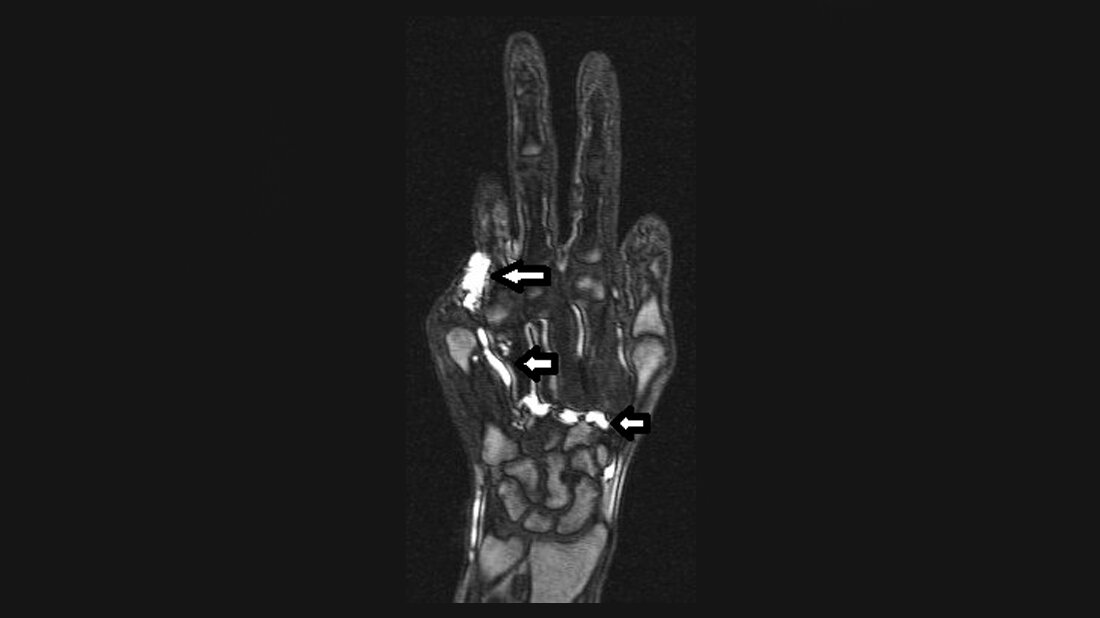

Anomalien und Normvarianten – Vaskuläre Veränderungen 2.27: periphere vaskuläre Malformation

Gefäßanomalien haben ein breites Spektrum der klinischen Präsenz. Das Management wird bestimmt durch die Klassifikation der vaskulären Malformation. Derzeit gibt es noch keinen Goldstandard in der Behandlung.

Schlüsselwörter: Gefäßanomalien, CT, MRT